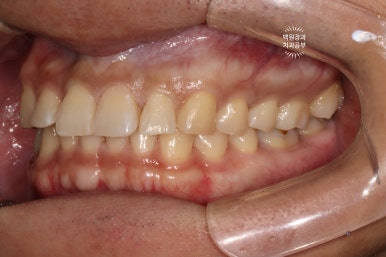

처음에 보여드렸던 우측 측면 사진입니다.

표면에 국한된 레진 변색의 경우 간단한 polishing 만으로 꽤나 만족스러운 결과를 얻을 때가 많습니다.

레진 재료의 특성상 표면이 '다공성'이기에 은근히 변색이 자주 오는데 (대부분은 bonding에 관한 이슈겠지만) 정말 표면 레진만 살짝 벗겨주면 되는 경우도 꽤 많거든요~ 이런 경우 비용은 거의 0원에 가깝습니다.

좌측 측면 사진에서 치료 결과가 더 극명하게 드러나는 것 같습니다.

사실 이 정도로 충치가 진행되시면, 기본적으로 국소마취가 필수입니다.

국소마취에 대한 영향으로 잘~ 보시면 잇몸이 조금 더 하얀 상태인 것을 보실 수 있죠? 치과용 리도카인 국소마취제는 약간의 에피네프린이 첨가되어 있어, 혈관수축을 유도하고 치료 시 출혈이 최소한이 되게끔 도와줍니다.

어쨌든~ 3M 레진의 자연스러운 색감으로, 아주 만족스러운 치료결과를 얻을 수 있었습니다.